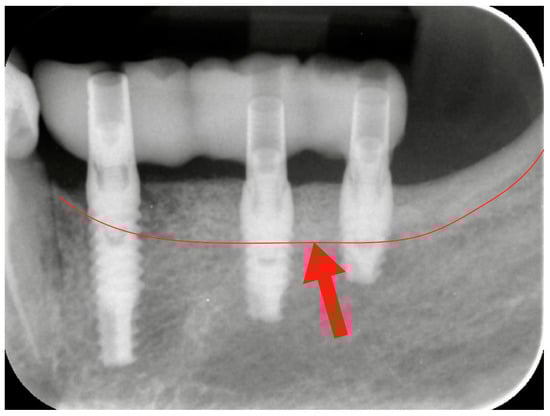

Figure 4. Radiographic check-up after the provisional resin restoration placement. The red line and the red arrow show the bone level before the vertical bone augmentation. The bone portion above the red line represents the amount of the vertical regeneration.